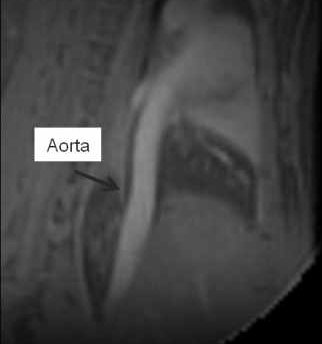

The Core facility Small Animal Imaging operates an ultrahigh field 11.7T MR imaging and spectroscopy system by Bruker (BioSpec 117/16) equipped with high-sensitive cryogenically cooled receive coils and multi-channel capability. It provides technology for neurological, abdominal and thoracic imaging in mice, rats and tissue samples. The means for physiological gating enables high-quality quantification of cardiac and other functional parameters. Advanced rapid MR spectroscopy (MRS) facilitates the study of a multitude of metabolic processes.

- To investigate high-field functional cardiac imaging

High Resolution Cardiac Imaging